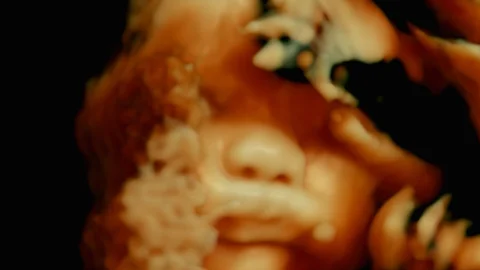

Un film-trip qui prend autant aux tripes par son aussi stupéfiante qu’inédite immersion dans le corps humain que par sa dissection de souffrances sociales.